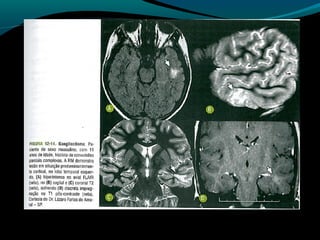

Astrocitoma subependimário de

células gigantes

Raro,

Circunscrito;

Benigno;

De crescimento lento;

Associação com esclerose tuberosa!

TC:

Próximo ao forame de Monro (mas existe localização

atípica);

Expansiva e >1,5cm;

Iso ou hipodensa; pode ser heterogênea e apresentar

calcificações;

Realce intenso pelo contraste;

RM:

Baixo sinal em T1;

Alto sinal em FLAIR e T2 (ou heterogêneo se

hemorragia ou calcificações);

Regra: realce intenso e difuso pelo Gd;

RM:

Geralmente sem disseminação pelo LCR;